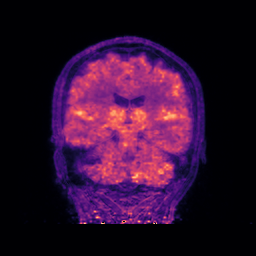

| [*] | The above dynamic transaxial and coronal images show the activity of 18F-florbetapir during the one-hour dynamic acquisition. Note that the signal in the brain white matter dominates over the signal in the grey matter towards the end of the acquisition, which is a typical presentation of a negative amyloid beta (Abeta) scan. |